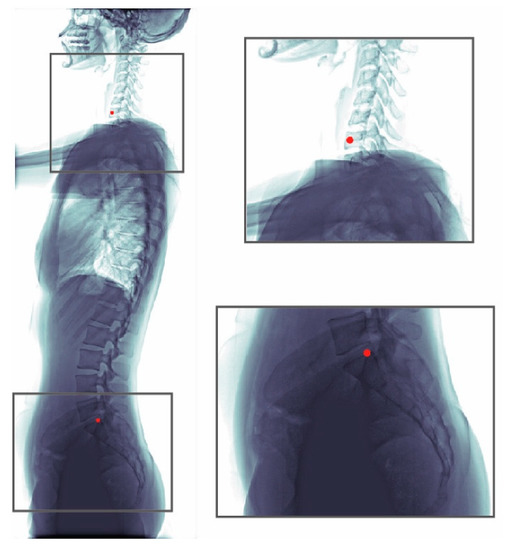

We selected the best model ( σ   =   1.57 , heatmap type = exponential) based on the absolute error of SVA. This model can be applied to patients of different age groups and with various clinical conditions, including patients with or without implants (Figure 10), having scoliosis, or degenerative changes (Figure 11).

Figure 11. Examples of predicted images of different clinical conditions. These images include patients of: (a) ages 8; (b) age 23; and (c) age 63, who also present with degenerative change.